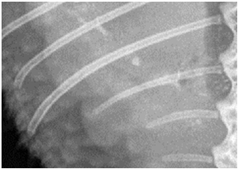

For this study, exclusively skeletal structures were examined. Four different structures (femur, ribs, vertebra, and phalanx) were chosen based on different bone architecture or features such as the differentiation of bone to soft tissue and surroundings (Table 3). The femur was essentially chosen to evaluate the differentiation between corticalis and spongiosa, joint structures were evaluated based on the left front phalanx, and the last left rib was used to further evaluate the details and structure of the corticalis. For each anatomical structure, four different characteristics (Table 3) were evaluated using a four-scaled scoring system, ranging from 1 (optimal evaluation) to 4 (insufficient evaluation). Scoring systems were used according to the modification of Körner, M. et al. [25] (Table 4).

In all four criteria, comparisons of D25% to D100% reached significantly lower scores than the D50% to D100%. The only exception was the phalanx using the CRP, but this was still nearly significant. The ribs showed the least significant difference between scores after the dose reduction. In both CR systems, a significant difference in scoring was only seen after the dose reduction from D100% to D25%, and in the FP system, a reduction from D100% to D50% already scored significantly different. The vertebra always scored significantly less with decreasing dosages independently of the radiography system used. For the phalanx, a dose reduction led to significantly lower scores in all comparisons for FP and CRN, but using the CRP, no significant difference was seen comparing the different dosages used. The femur showed different results with each system used. The CRN comparison of D50% to D25% showed no significant difference, while D100% to D50% and D100% to D25% did, with the latter even being highly significant. Using the CRP, only the comparison of D100% to D25% was significant, whereas while using the FP, every comparison of dosages showed a significant to highly significant difference in scoring (Table 5).

4.3. Effect of Dose Reduction

Data showed that in every system, a dose reduction led to significantly worse scores for most of the criteria, especially in the “double” reduction from 100% to 25%. Regarding the criteria, the vertebra seems to be the most sensitive structure with significantly worse scores after every reduction with each system used. In contrast, the ribs showed the least influence of the dose reduction, only receiving decreased scores after a reduction of 25%. The effect of dose reduction for the criterion femur varied. In the ribs and femur, the reviewers had to evaluate the differentiation between the bone, whilst in the criteria for vertebra and phalanx, the demarcation to the surrounding tissue and joint space was addressed. The vertebra and phalanx are much more delicate structures than the femur and rib, indicating a possible greater impact of dose reduction on smaller structures. In particular, the joint space with a fine surface and superimpositions of other structures could therefore be more affected than more solid structures such as the femur. The ribs are much more delicate than the femur, impeding the evaluation of this criterion and possibly leading to a greater impact in dose reduction, again indicating a greater influence on smaller structures. In contrast, the femur showed the best scores, indicating that the thicker and bigger the structure, the higher the chance of being able to evaluate variances.